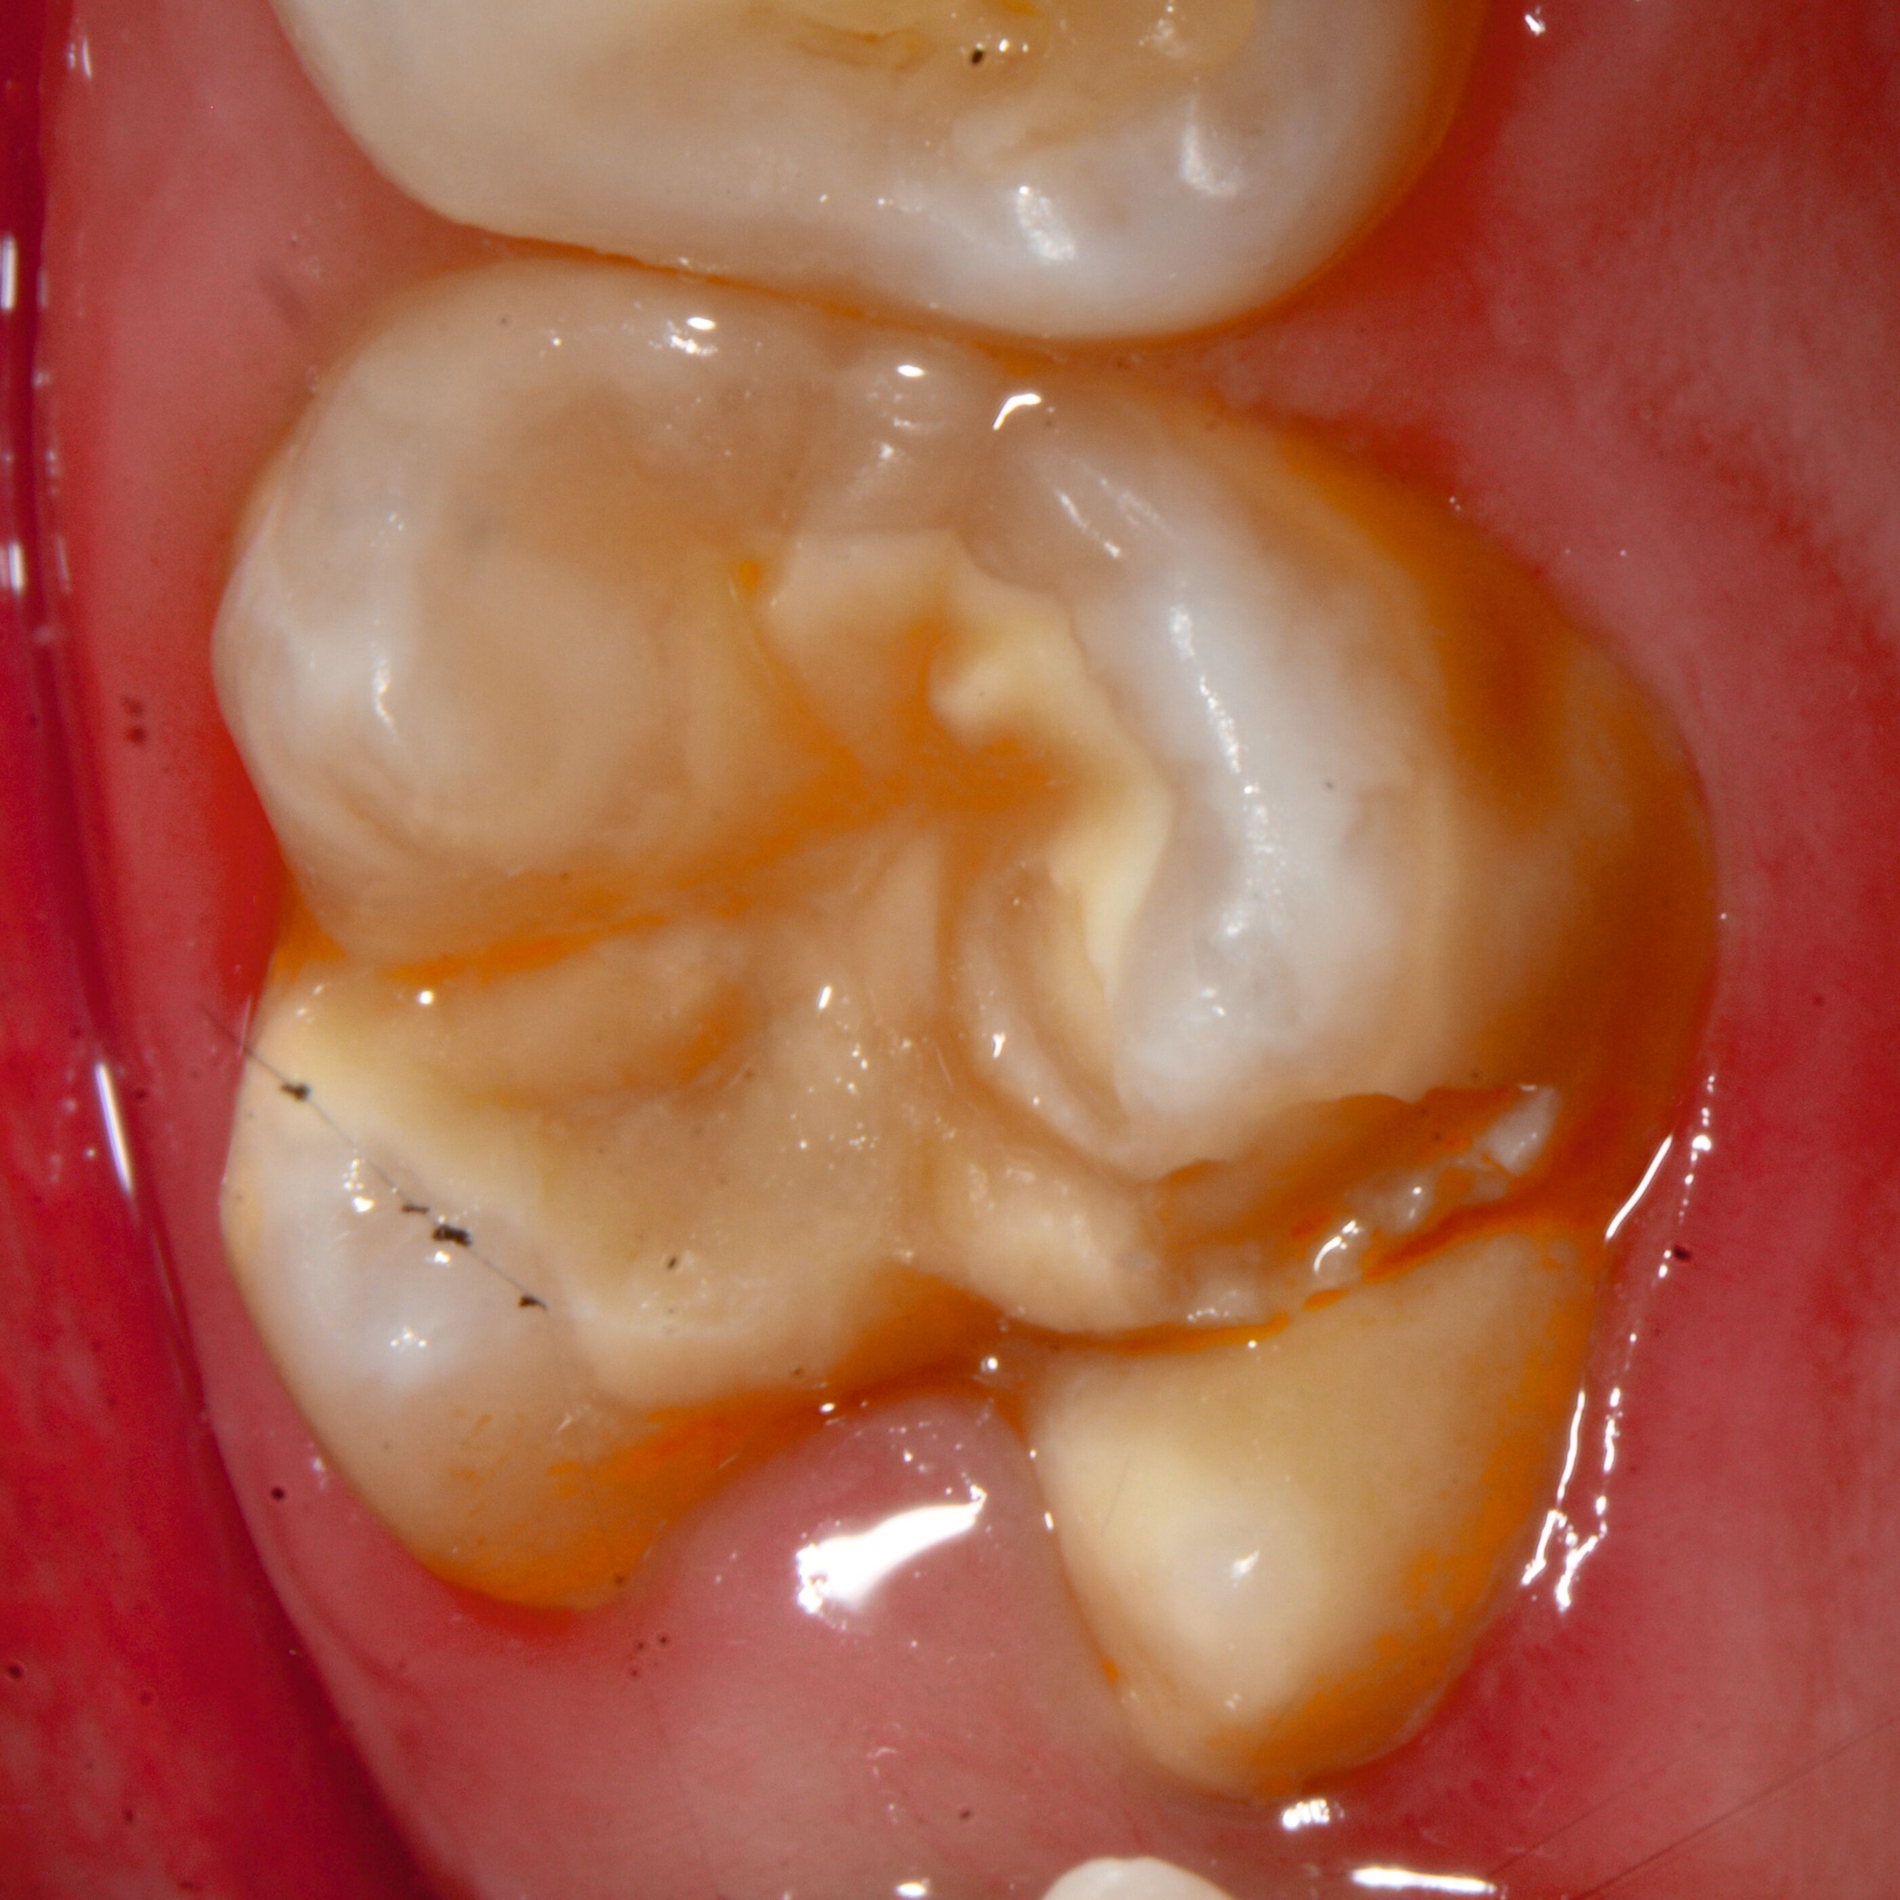

Das klinische Erscheinungsbild an bleibenden Zähnen zeigt typischerweise weißlich-gelbe bis gelblich-braune Opazitäten, die zumindest in einigen Bereichen durch eine scharfe Abgrenzung (engl.:„demarcated opacities“) zum gesunden Zahnschmelz charakterisiert sind (Abbildungen 3 und 4). Die abgegrenzten Hypomineralisationen befinden sich mehrheitlich im Bereich der inzisalen Kronenhälfte unabhängig von dem Auftreten an Front- oder Seitenzähnen. Die Ausprägung am Zahn kann dabei auf einzelne Areale oder Höcker begrenzt sein.

Bei einer schwerwiegenderen Ausprägung sind Zahnflächen vollständig betroffen, mitunter alle Zahnflächen an einem Zahn. Die Verteilung in der Dentition beziehungsweise an den Indexzähnen ist gleichermaßen variabel und betrifft nicht nur die Defektgröße, sondern auch die Farbe und Festigkeit. Was die Festigkeit betrifft, gilt als die Faustregel: Je dunkler die Farbe des Schmelzes, umso weicher beziehungsweise poröser und damit minderwertiger wird dessen Qualität sein. Damit reduziert sich seine kaufunktionelle Belastungsfähigkeit, was insbesondere an ersten bleibenden Molaren von klinischer Relevanz ist.

Für die Dokumentation und Klassifikation der MIH wurden verschiedene Systeme vorgeschlagen. Als historisch und veraltet gilt der (modifizierte) DDE-Index. Demgegenüber haben die Kriterien der EAPD – abgegrenzte Opazitäten (Abbildung 3 und 4), Schmelzeinbrüche (Abbildung 5), atypische Restaurationen (Abbildung 6) – mittlerweile die weiteste Verbreitung gefunden. Diese wurden 2003 erstmals zur Beschreibung der MIH auf empirischer Basis publiziert [Weerheijm et al., 2003] und den Jahren 2010 und 2022 im Rahmen der damaligen MIH-Workshops bestätigt [Lygidakis et al., 2010; 2022].